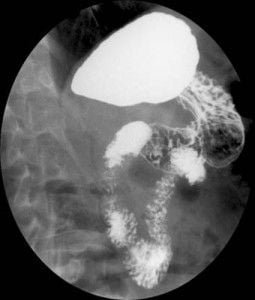

Noticias y Articulos Tránsito esofagogastroduodenal (E.G.D.) – Parte II 21 junio, 2012 Tidito Imágenes Transito Esofagogastroduodenal (E.G.D.) Seriadas Bulbares Duodeno en Anteroposterior